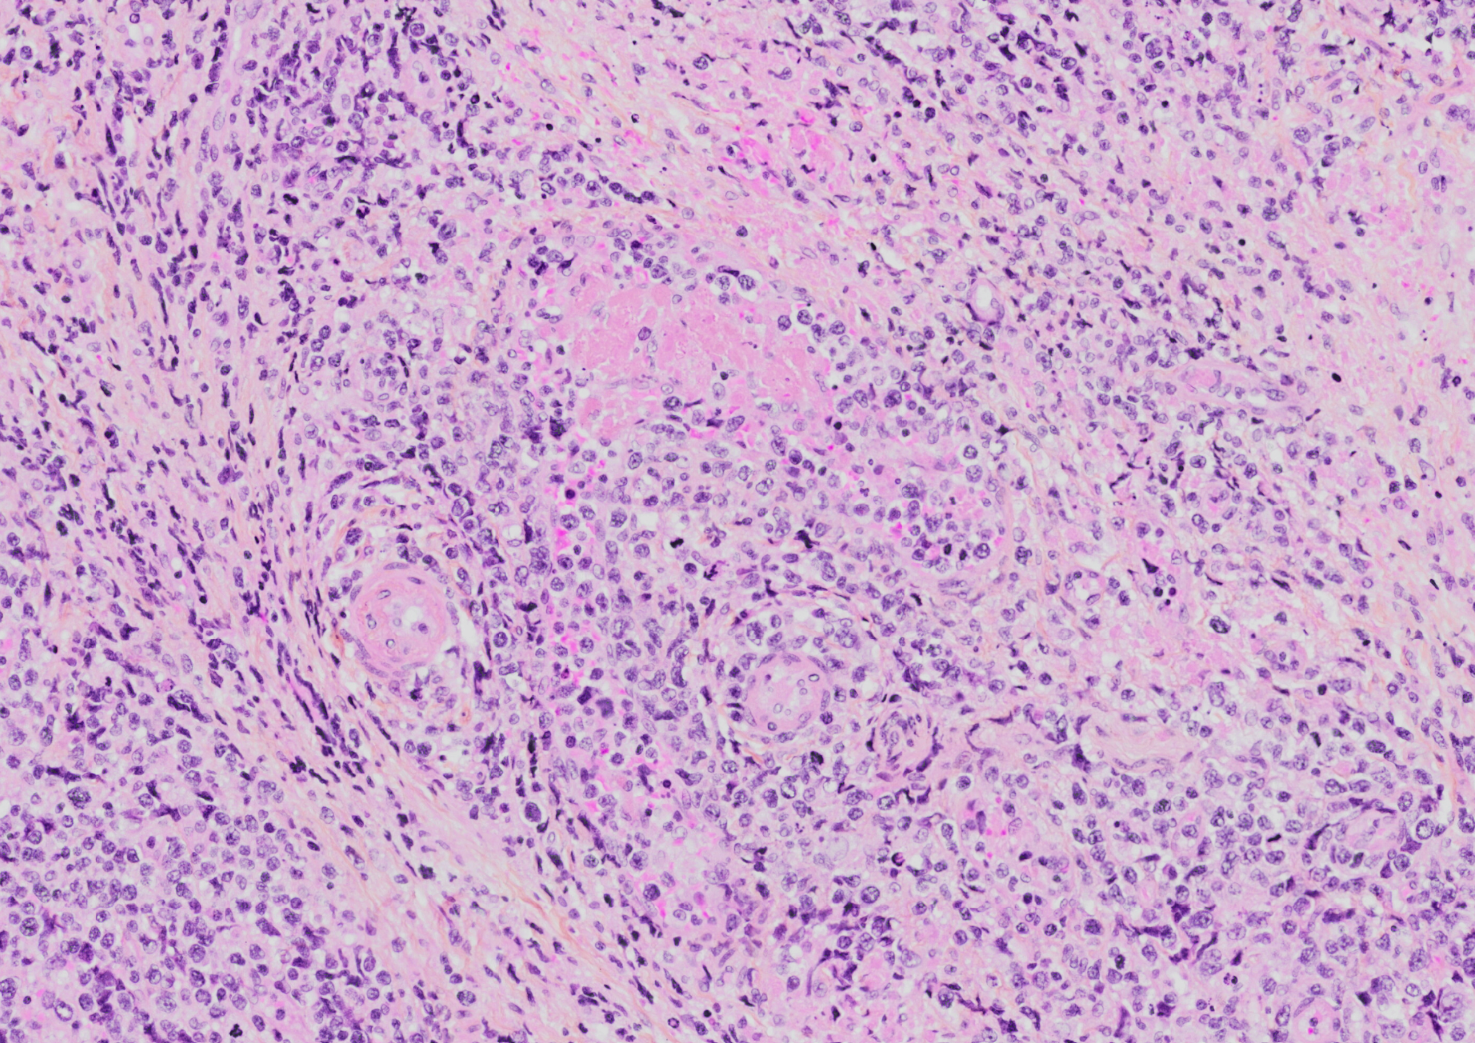

Morphologic Features

- Diffuse infiltrate composed of admixture of small, medium, or large and anaplastic cells.

- Cells have irregularly folded nuclei and moderate pale cytoplasm.

- Loss of mucosal glands.

- Angiocentric and angiodestructive growth pattern with coagulative necrosis.

- Usually see apoptotic cells and mitotic figures

Pitfalls:

- Mucosal ulceration and superimposed inflammation can mimic an inflammatory process, particularly in less aggressive cases[10].

- Pseudoepitheliomatous hyperplasia of the overlying mucosal epithelium can mimic squamous cell carcinoma[11][12].